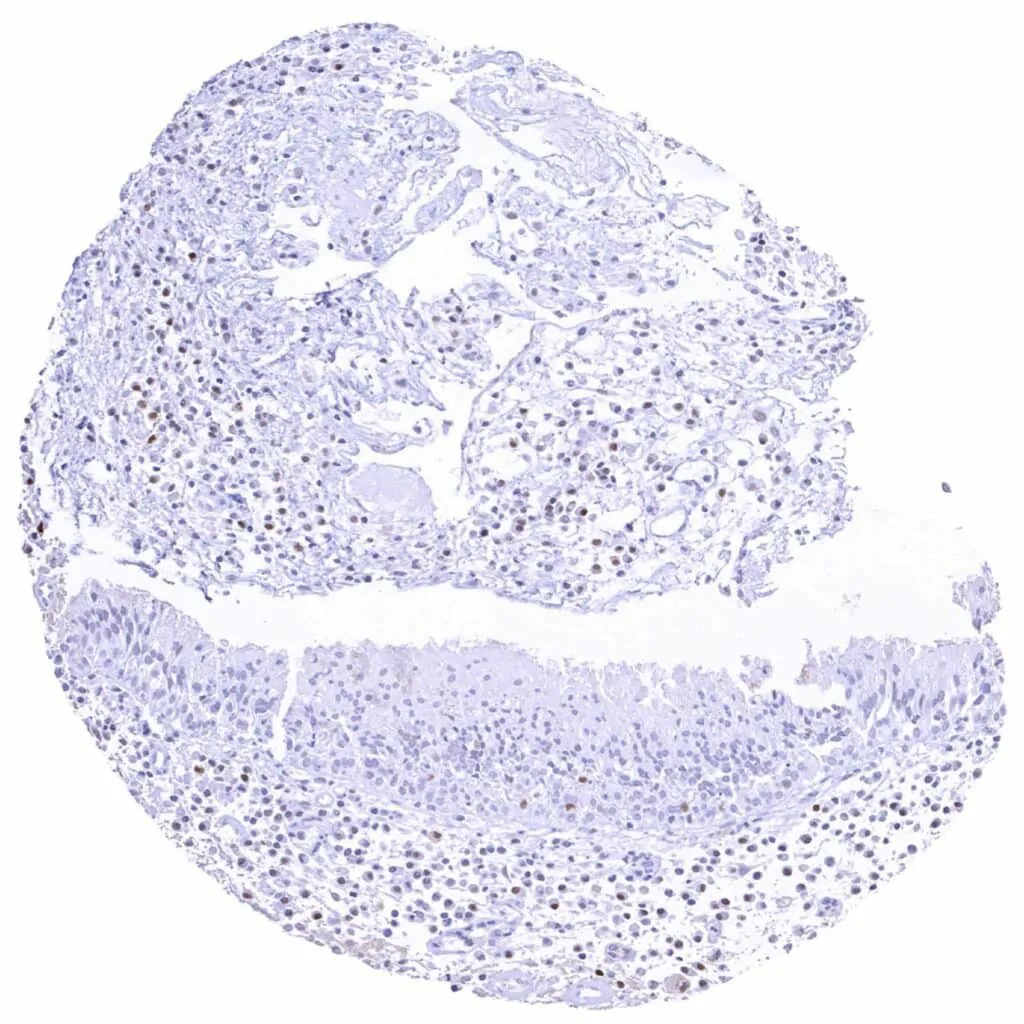

Tonsil – Weak to moderate Cyclin E1 staining of a fraction of lymphocytic cells, especially in germinal centres

Tonsil, surface epithelium – Strong Cyclin E1 staining of most squamous epithelial cells in the upper half of the surface epithelium